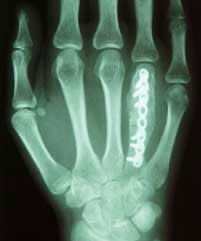

Tumor ausgeräumt, verpflanzter

Knochen nach 6 Wochen eingeheilt.

Platte wurde nach 6 Monaten entfernt.

6 Wochen nach der Operation freie Funktion.